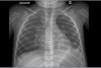

On clinical examination, she was eupneic (breath rate 27/min) with 100% oxygen saturation. She had no chest deformity, pulmonary auscultation found crackles in the left lower lobe. Fold candidiasis was visible. Chest radiograph (Fig. 1) showed left inferior opacity, consistent with partial atelectasis, associated with bilateral bronchial thickening. CT scan (Fig. 1) confirmed partial atelectasis of the lingula, medial segment of the middle lobe, anterobasal segment of the left lower lobe and small bronchiectasis of the anterior segment of the left upper lobe. Fiberoptic bronchoscopy showed thick, diffuse secretions, predominantly in the left bronchial tree (lingula); bronchoalveolar lavage was inflammatory (79% of neutrophils) with 108UFC/ml Haemophilus influenzae. Gastro-esophageal endoscopy revealed erythematous esophagitis with white deposits, consistent with candidiasis (confirmed by biopsy). The main etiologies of chronic lung suppurative disease were ruled out: